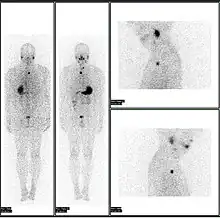

A nuclear medicine parathyroid scan demonstrates a parathyroid adenoma adjacent to the left inferior pole of the thyroid gland. The above study was performed with Technetium-Sestamibi (1st column) and iodine-123 (2nd column) simultaneous imaging and the subtraction technique (3rd column).

A nuclear medicine SPECT liver scan with technetium-99m labeled autologous red blood cells. A focus of high uptake (arrow) in the liver is consistent with a hemangioma.